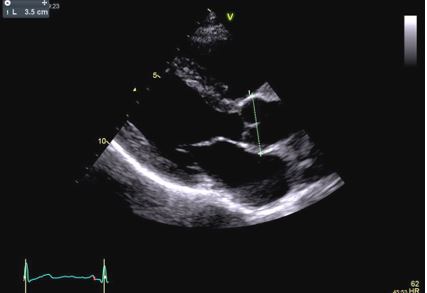

In our patient transthoracic echocardiography revealed normal diameters of the left ventricle with mild septal hypertrophy (EDD: 51 mm; ESD: 31 mm; IVS: 12 mm; PW 10 mm) with mild enlargement of the right ventricle (mid-cavity diameter: 37 mm), with normal biventricular systolic function. However, TTE revealed a tricuspid aortic valve with dilatation of the aortic root (44 mm, Z-score >2: Z=4.2). Ascending Aorta and aortic arch diameters were normal in absolute values (35 mm and 32 mm, respectively) and when keeping into consideration body size.

After a year, our patient underwent TTE that showed an aortic root dimension of 44 (Figure C), stable in comparison with the previous evaluation, with no modification of ascending aorta measurement and no LV enlargement (Figure A and B). He continues with yearly follow-up, continuing with personalized physical activity previously prescribed.